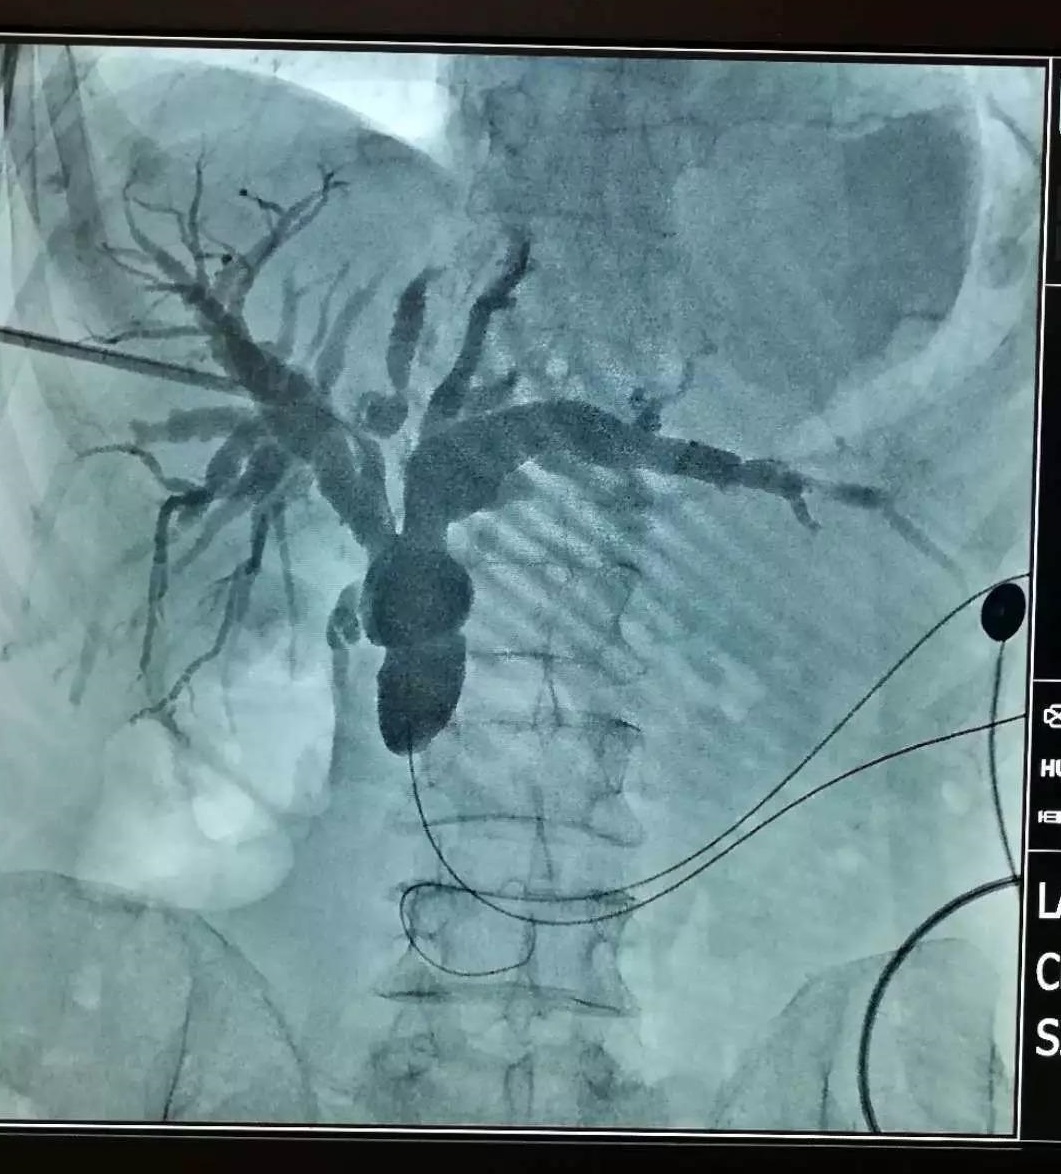

对于入路选择,由于胆肠吻合口狭窄的患者多出现肝内胆管扩张,通常优先选择行PTCS术。一般优先选择扩张的左侧肝内胆管作为穿刺入路,避免胆道镜进出角度过大造成操作困难。目前,狭窄扩张方法有高频电刀切开、球囊扩张或支架等,均能取得满意效果。首次手术一般仅建立入路,除非患者严重感染,否则均将狭窄扩张放至后期经皮胆道镜术中。胆道镜下先针刀切断缩窄的纤维环,然后置入球囊进行扩张。狭窄环较短的患者,宜选择柱状水囊;如狭窄环距离较长,则宜选用扩张力度更大的球状水囊。针刀联合球囊的方式不仅可以将纤维瘢痕组织切断,亦可运用球囊扩张更好地进行狭窄整形,在不同的吻合口狭窄处理上更灵活。多数病例经过2-3次扩张,胆肠吻合口可扩张至0.7cm以上。

值得注意的是,胆肠吻合口狭窄患者常合并较多肝内胆管结石,在结石未有效清除前胆道镜不能直接到达胆肠吻合口,不能及时、有效地对胆肠吻合口狭窄进行扩张治疗。另有部分胆肠吻合口狭窄患者的肝内胆管扩张并不明显,导致穿刺困难无法行PTCS术;或者部分患者虽穿刺成功,但胆道镜无法有效到达狭窄的胆肠吻合口。而ERCP技术的发展,使这部分患者免于再次手术治疗。内镜到达吻合口后,可对吻合口进行球囊扩张,植入胆道内引流管并进行取石操作。对于吻合口炎性或瘢痕狭窄的患者,也可植入金属支架,对狭窄进行缓慢而持续的扩张6-12月,有利于防治吻合口扩张后的再次狭窄。